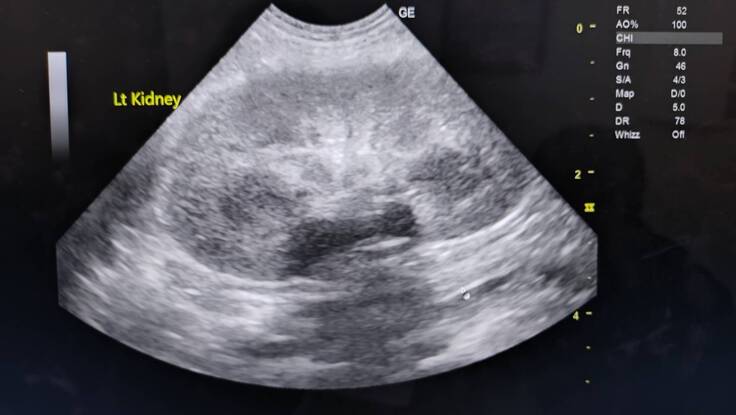

エコー写真→キラキラ白く写っているのが菌、脂肪や結石様のもの浮遊物

腎臓結石あり→悪さはしていない

右、左の腎臓も変形などなし

今のところ腫瘍とかは確認できるものはなさそう